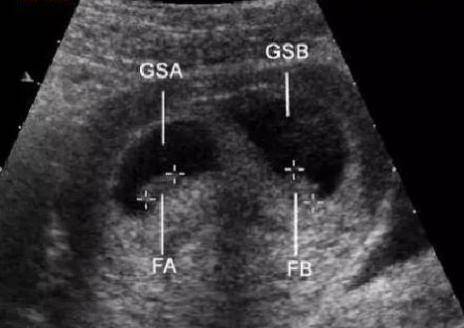

一个孩子太孤单,两个孩子刚刚好,所以很多人就有了生双胞胎的欲望。可是生双胞胎的概率很低,那么怎么知道自己怀的是不是双胞胎呢?...